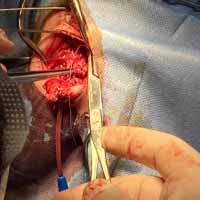

Bodrum Yalıkavak'ın seçkin veteriner kliniği olarak, minik dostlarınızın cerrahi ihtiyaçlarında uzman kadromuzla hizmetinizdeyiz. "Yalıkavak veteriner cerrahi" arayan pet sahiplerinin güvenle tercih ettiği merkezimizde, modern cerrahi yöntemlerle başarılı operasyonlar gerçekleştiriyoruz.

Ortopedik cerrahi oldukça titizlik ve özen gerektiren cerrahi uygulamalardır. Diğer cerrahi disiplinlere nazaran asepsi ve antisepsi (sterilizasyon) konusunda ASLA hata kabul etmez. Eğer bu aşamada özensiz davranılırsa, postoperatif süreçte kemik dokunun iltihaplanmasına neden olup, kemiklerin kaynaması gecikmiş olur.

Aslında bu cerrahi alan oldukça geniş bir alanı kapsamaktadır. Fakat siz yırtılan ya da kesilen deriye uygulanan cerrahi işlemler olarak düşünebilirsiniz. Daha detaylı anlatmak gerekirse; Örneğin; Erkek bir kedinin üriner taşlarından dolayı sondayla denenmesine rağmen açılmayan idrar kanalına yapılan dişileştirme operasyonu (perineal üretrostomi) da bir yumuşak doku cerrahisi operasyonudur.